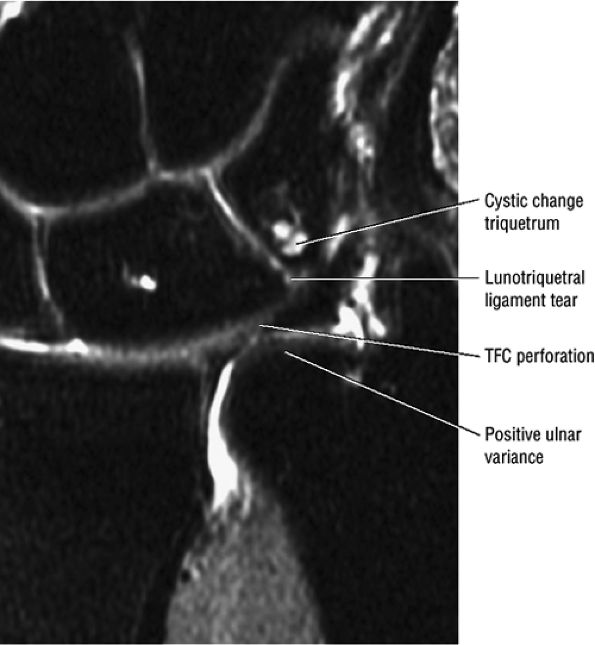

|

FIGURE 10.36 Triangular Fibrocartilage.

ulnar styloid can chronically impact the proximal triquetrum.